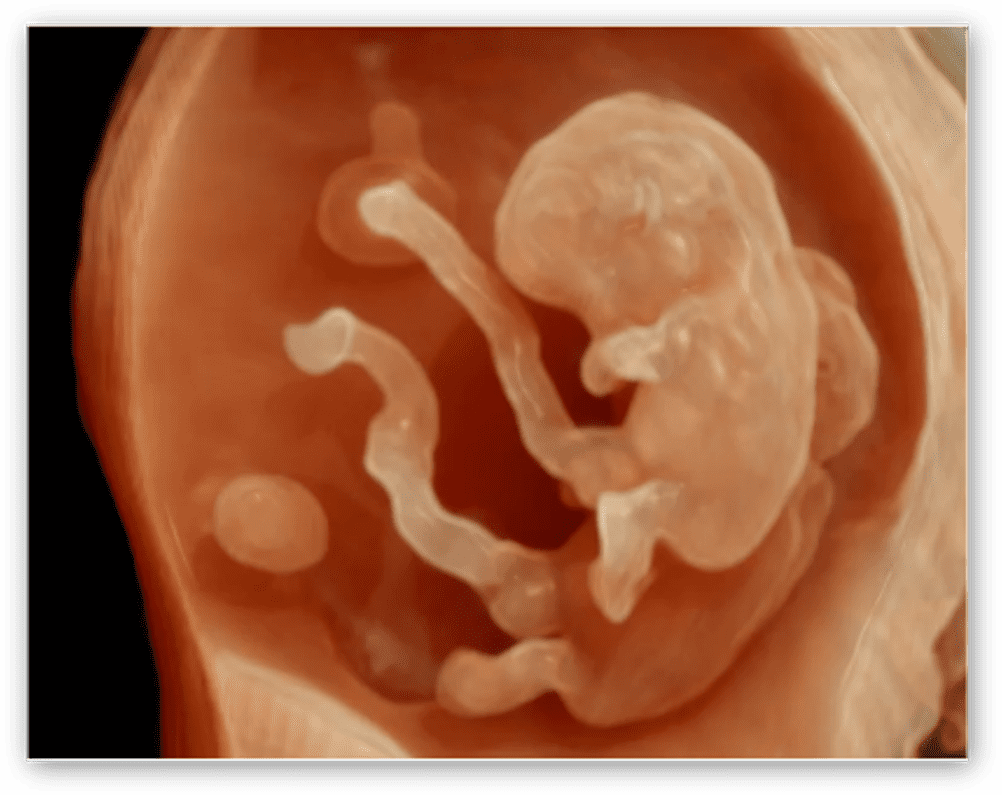

HDlive™ Silouette: tecnologia che permette aggiungere ai rendering realistici l’effetto trasparenza di tutti i volumi acquisiti (in 3D e 4D) per una migliore visualizzazione delle strutture e degli organi interni.

HDlive™ Studio+: espande le funzioni di già disponibili in HDlive™ offrendo la gestione di tre sorgenti fotometriche luminose indipendenti con tre diversi tipi di luce (direzionale, puntiforme, spot) e presenta una funzione speciale di rappresentazione per visualizzare il liquido amniotico.